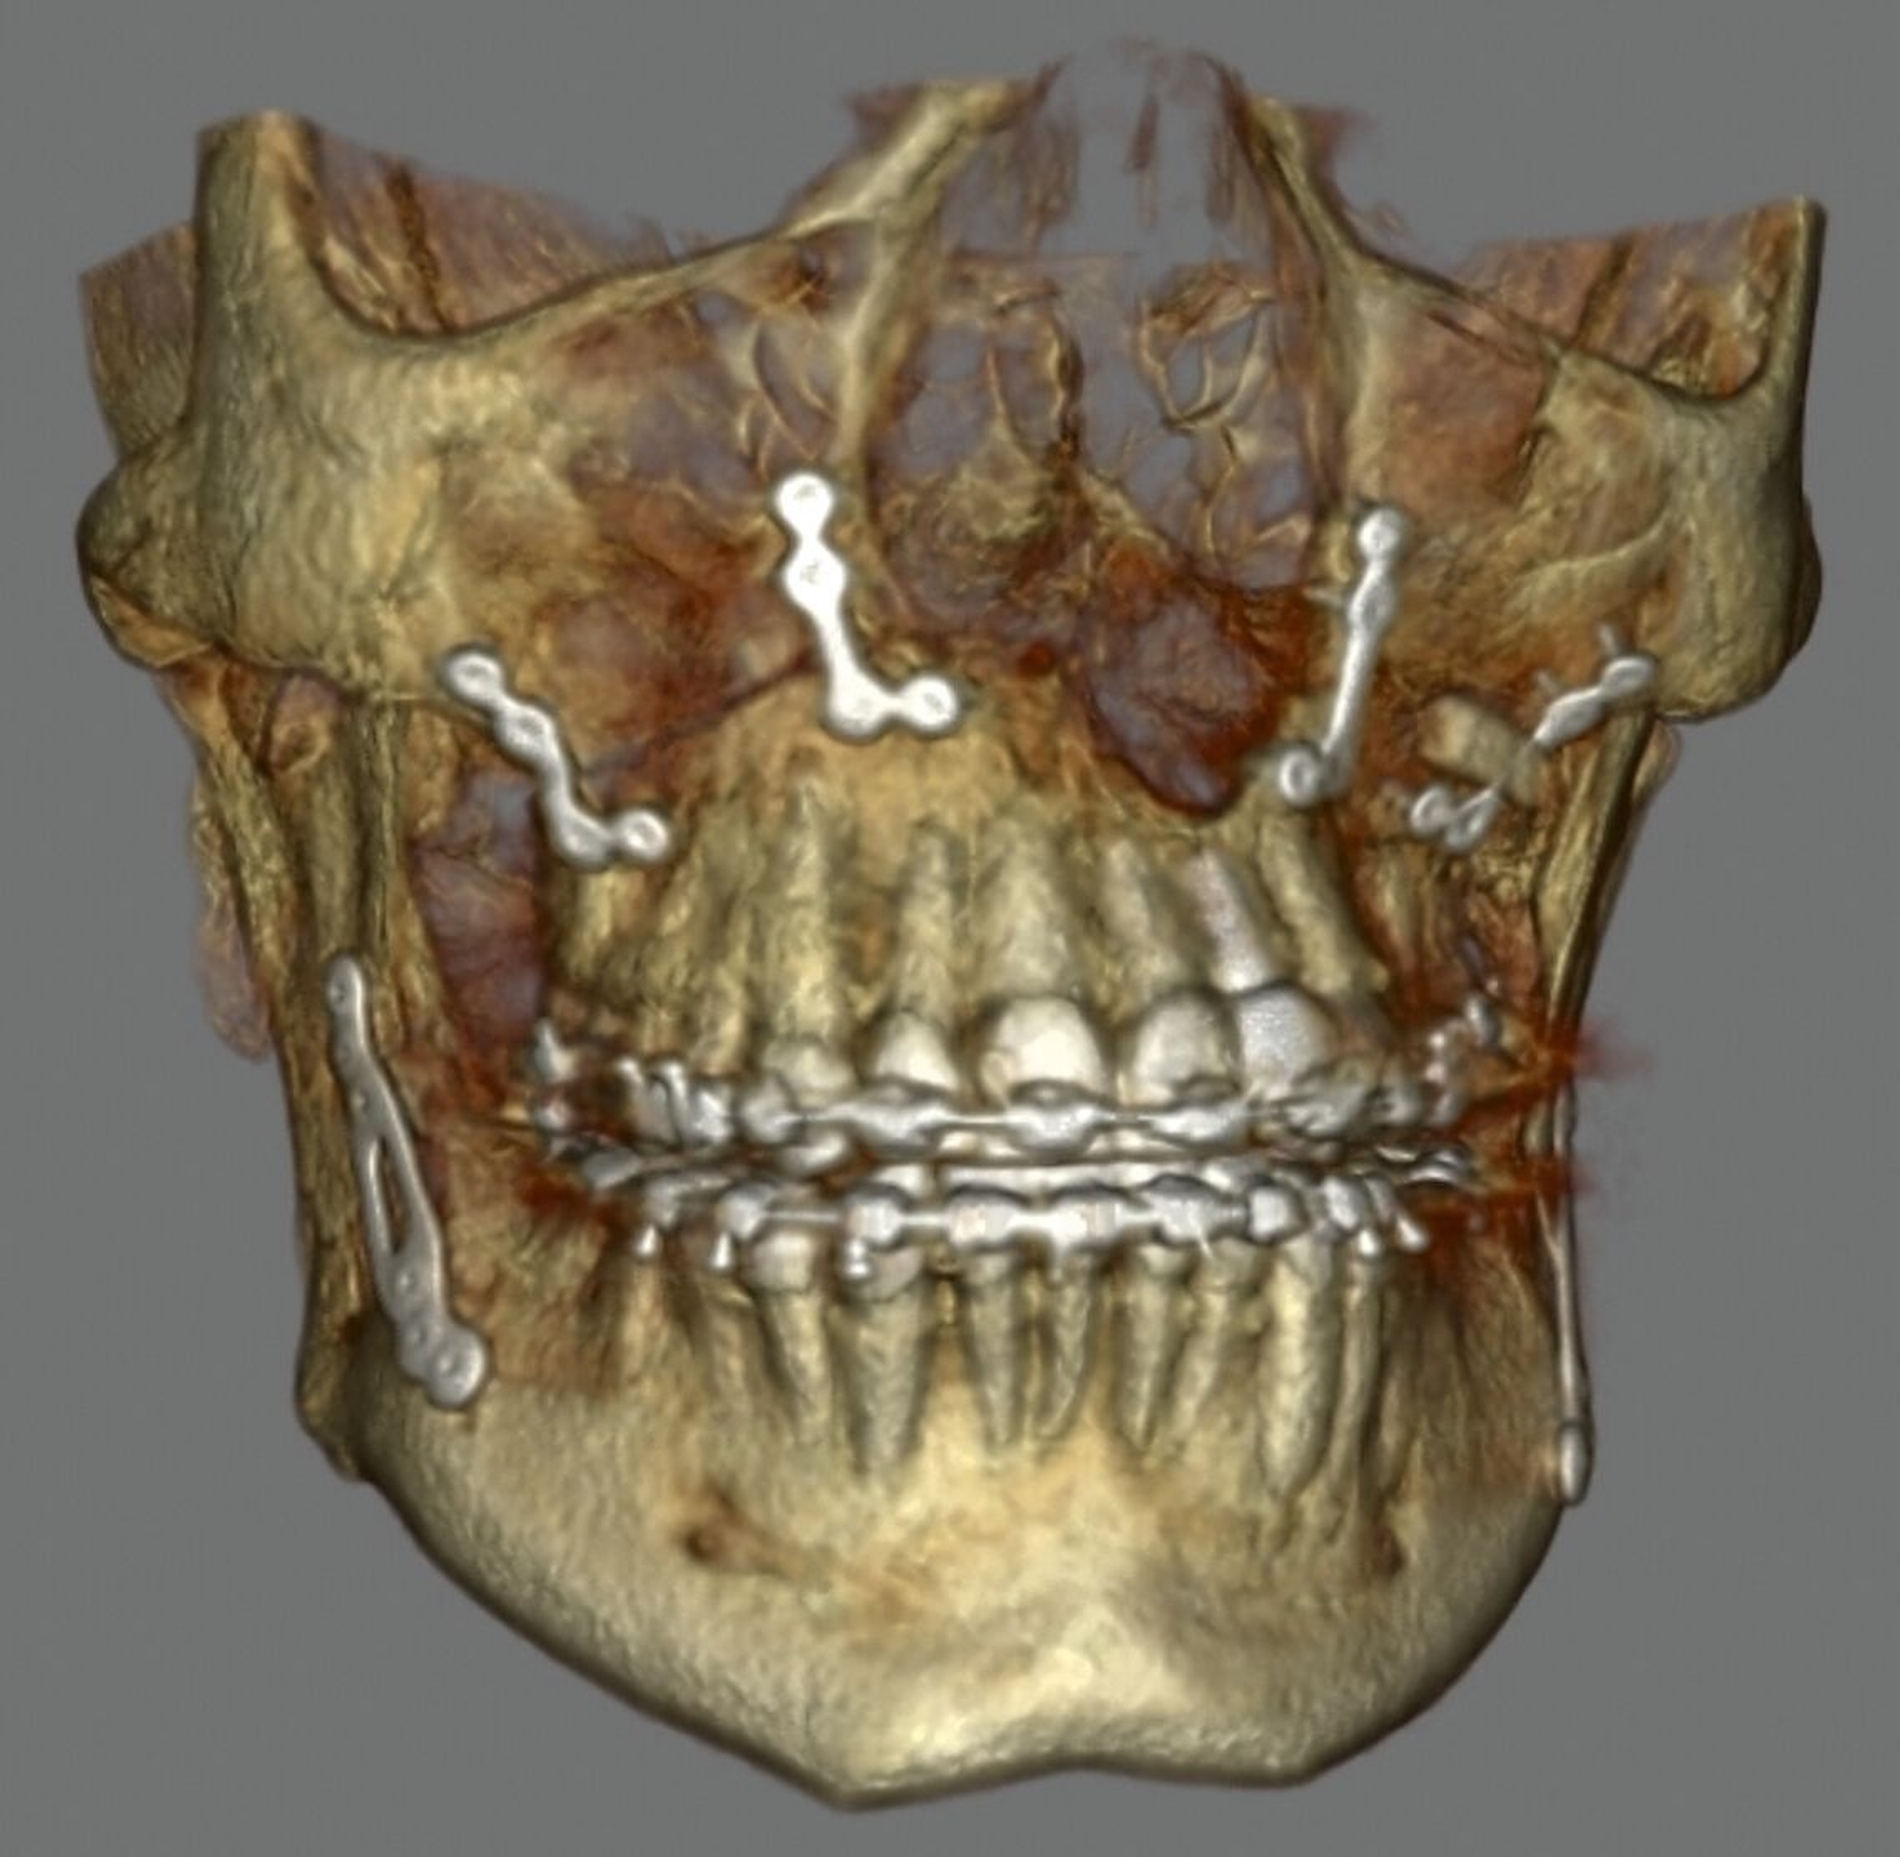

Der Eingriff konnte noch im selben Jahr komplikationslos in Intubationsnarkose durchgeführt werden. Nach digitaler Planung durch Matching der präoperativen DVT-Aufnahmen und der Intraoralscans wurden die Splinte für die Operation 3-D-gedruckt, nachdem die Zielokklusion festgelegt worden war. Der Oberkiefer wurde in der Le-Fort-I-Ebene osteotomiert und um 0,5 mm nach anterior und um 2,5 mm nach rechts verlagert. Durch die Kippung entstanden eine rechtsseitige dorsale Impaktierung um 1,5 mm und eine linksseitige Kaudalverlagerung um 1 mm. Der Unterkiefer wurde um 1 mm nach anterior verlagert, wobei es zu einer Schwenkung von 5 mm nach anterior links und um 2 mm nach posterior rechts kam (Abbildung 4).

Sechs Wochen postoperativ begann eine adjuvante Behandlung mittels Physiotherapie und Lymphdrainage. Sechs Monate postoperativ erfolgte planmäßig die Entfernung der Osteosyntheseplatten. In diesem Rahmen wurde auf Wunsch der Patientin zusätzlich eine Augmentation der Ober- und Unterlippe sowie der Nasolabialfalten mittels autologem Fett aus dem Bauchbereich vorgenommen. Zudem erfolgten eine Anhebung des linken Mundwinkels und eine Narbenreduktion am Hals mittels CO2-Laser.